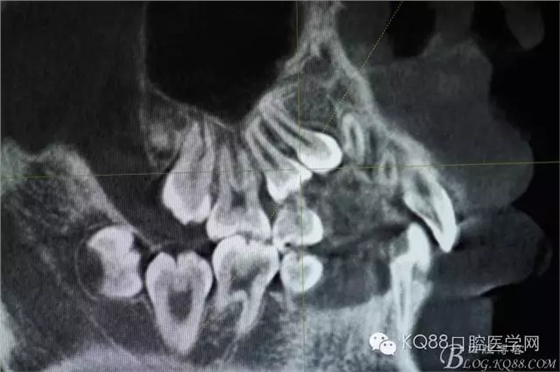

圖4.從局部影像,可以看出14牙冠位于15牙冠與13牙根之間。